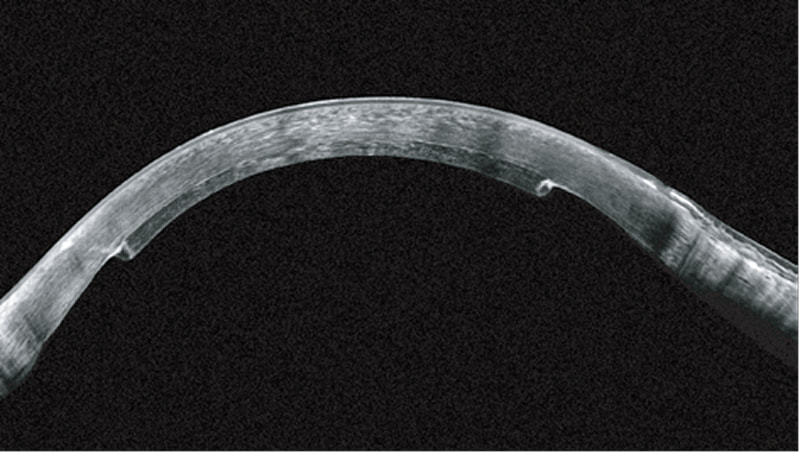

上皮厚マッピングは、レーザーによる視力矯正術を行う前の角膜拡張症リスク評価をサポートします。

特に、初期の円錐角膜とコンタクトレンズ装用による角膜形状変化の識別に役立ちます。

上皮のリモデリングなどのレーザー視力矯正術(LVC)後の変化を評価するために重要な、角膜上皮の厚さを精密に測定することが可能になります。

特に角膜の生体力学的特性と組み合わせると有力な手段となり角膜拡張症のリスク全体に関する包括的な洞察を可能にします。